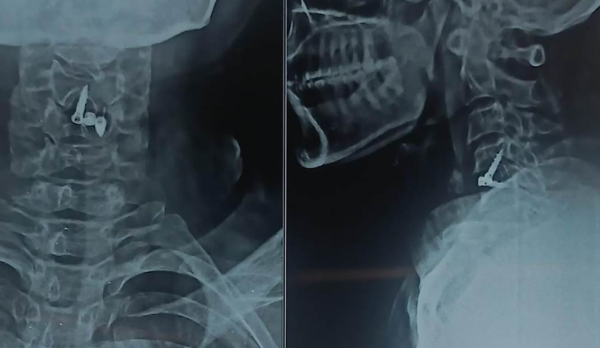

Posted on Nilesh KaduTrustindex verifies that the original source of the review is Google. I visited Dr. Nitish Agarwal for my severe back pain and shoulder issue. He checked my MRI very carefully and gave the perfect diagnosis. Yesterday, he performed the procedure (Root Block and Shoulder Injection), and it was completely painless. He is an expert and targeted the exact nerve point causing the trouble. Very helpful and humble doctor. Highly recommended for anyone with spine problems.Posted on Raju GorkhaTrustindex verifies that the original source of the review is Google. I was unable to make movement and suffered from right foot drop which is equal to halfway paralysis. Dr. Nitish Agarwal performed very fine microscopic surgery on L3, L4 & L5. After 90 days under his treatment I could go for a walk min. 6 kms a day, I have started my regular activities after 120 days. Thank you so much Dr. Nitish Agarwal sir.Posted on Pururaj GuravTrustindex verifies that the original source of the review is Google. I was suffering from severe back pain, and Dr. Nitish Agrawal has been extremely supportive throughout my treatment. He listened carefully, explained everything clearly, and guided me very well. His treatment has really helped me recover. He is one of the best spine specialists — highly recommended!Posted on Vinal AgrawalTrustindex verifies that the original source of the review is Google. I had consulted many doctors before Dr Nitish for my mother's spine issue,most recommended complex procedures and surgeries. Fortunately we found Dr Nitish and it has been life changing for my mother,she was in immense pain before the simple surgery he did. It's rare to find a surgeon who explains everything in detail and provides such exceptional care even after the surgery. I Would highly recommend him.Posted on Ajinkya MohadkarTrustindex verifies that the original source of the review is Google. My mother had sustained a fracture to her right hand wrist and we were worried about her recovery due to age factor. One of our family Doctor referred us to Dr. Nitish Agrawal and we visited Dr. Nitish Sir. Dr. Nitish sir ensured that my mother don't need a surgery and treated her by application of plaster (temporary and then cast-iron or Firm plaster) with certain orthopaedic treatment to hand and prescribed oral medication for ensuring recovery is faster without any surgery. Attaching the photo of xray which shows recovery of wrist bone which has rejoined and we are still continuing treatment to ensure my mother is fully recovered and is fit. Thank you Dr.Nitish Agrawal for your support.Posted on Samadhan LokhandeTrustindex verifies that the original source of the review is Google. Hi everyone, myself Samadhan. I was suffering from severe spine pain for a long time, and one of my friends suggested I visit Dr. Nitish Agarwal. Honestly, that was the best advice! Dr. Nitish listened to my problem very patiently, explained the cause in detail, and gave me the right treatment. I started feeling better within a short time. He is very polite, knowledgeable, and truly cares for his patients. I highly recommend Dr. Nitish Agarwal for anyone dealing with spine or back pain. Thank you, doctor, for your excellent treatment and support!Posted on POOJA JAGDALETrustindex verifies that the original source of the review is Google. Dr. Nitish Agrawal is an excellent spine specialist who patiently listens, explains the problem clearly, and provides the best treatment options.Posted on vipul pardeshiTrustindex verifies that the original source of the review is Google. Dr.Nitish sir is an incredible surgeon. I had excellent results from my recent spine surgery. The entire process, from consultation to recovery, was handled with professionalism and care. The outcome has been life-changing. I highly recommend Dr.Nitish agarwal to anyone in need of a spine surgeon.Posted on Deepak JadhavTrustindex verifies that the original source of the review is Google. A few months back I took treatment for my back pain from dr. Agarwal sir ...last 7-8 years i was suffering with low back pain,unbale to stand for more than 10 minutes..My low back hurts continuously, and also left leg pain was unbearable....i try every possible way of treatment from various suggestion...After several treatment...one of my relative suggested dr. Nitish Agarwal sirs name then I visited Dr. Nitish Agarwal sir in clinic. He suggested me x ray and MRI. On that basis he advise me caudal Block with root block with facet block for pain management. After block my pain goes with in a week. He advise me regular Physiotherapy at home. Now after regular exercise I am pain Free. Dr. Nitish Agarwal is a good doctor for any spine related problem.... Thank u dr. Agarwal Sir 🙏Posted on Kumar BTrustindex verifies that the original source of the review is Google. My wife had major infection in neck and lower back. She was bedridden. her legs and hands were weak. Then we admit her under Dr. Nitish Agarwal sir and did MRI. He explained that she is having major infection in cervical and lumbar spine. Due to infection her spinal cord is compressed so she was not able to walk. Then sir did operation for neck and removed infected tissue and spinal cord is freed and put a plate. Her lower back is treated with medicine only. She was given 2 months antibiotics by saline and 5 months oral antibiotics were given. He also advised regular exercise. After 15 days of surgery she started walking with support. Now after 1 year she is completely alright and walking like a normal person. She is regularly doing all her activities. Now she can also travel by 2 wheeler. Thank you to Dr. Nitish Agarwal sir for his expert work in spine. I recommend Dr. Nitish Agarwal for any spine related problem.